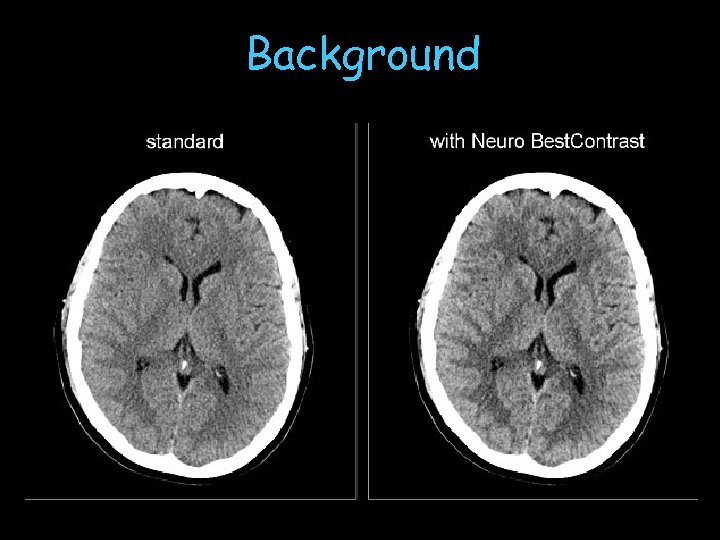

Background CT images traditionally reconstructed using filtered back projection techniques (FBP) FBP limitations: geometry, data completeness, radiation dose Increased spatial resolution is directly correlated with increased image noise

n MBE improves CNR of specific image features n n Head: gray/white matter differentiation (CNR gain up to ~40%) CNR improvement can be translated into radiation dose reduction n n 30% less dose demonstrated in example realistic in general: 20% (further clinical studies needed) Raupach, et al.

Background